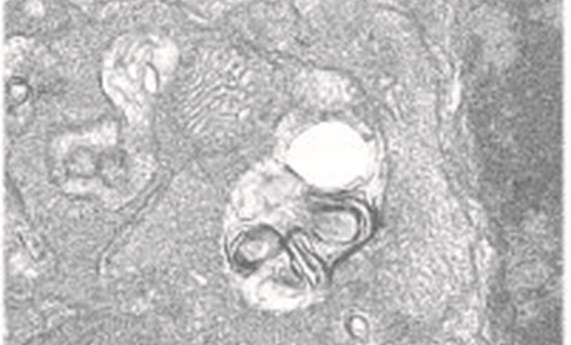

La autofagia resuelve la inflamación retiniana causada por el déficit en IGF-1 en el ratón-

La autofagia resuelve la inflamación retiniana causada por el déficit en IGF-1 en el ratón